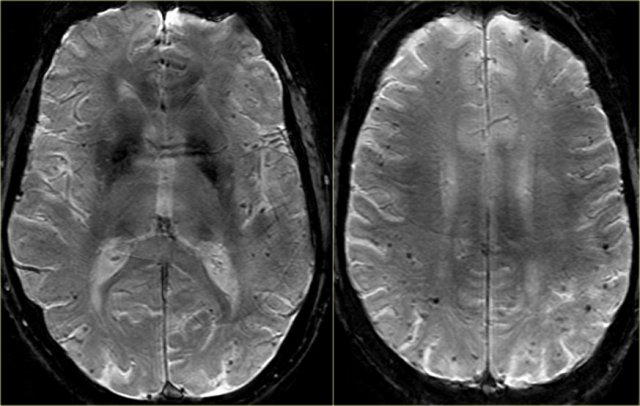

Vascular dementia, no medial temporal lobe atrophy. Vascular dementia, no medial temporal lobe atrophy.

In most patients with VaD there is diffuse white matter disease with large confluent lesions (Fazekas 3).

The images are of a patient who had VaD, but the medial temporal lobe was normal.